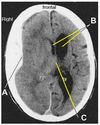

Label this.

What are the sutures of the skull and what are the joining points you need to know?

What suture is this?

Coronal suture

Sagittal suture

Lambdoid suture (parieto-occipital suture)